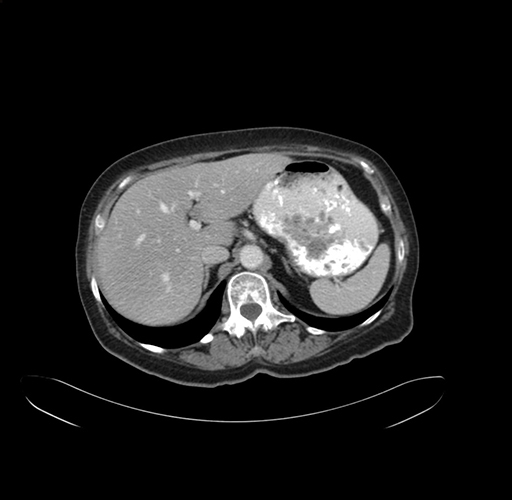

Axial Venous